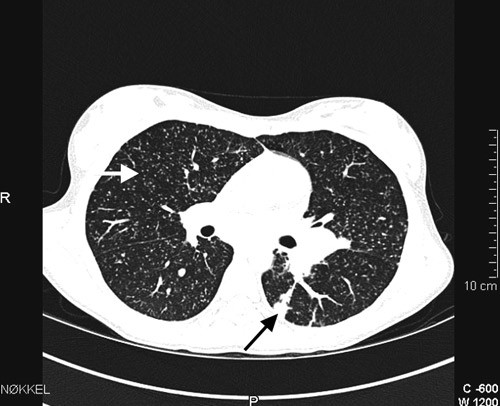

Ved innkomst var det normal respirasjon og normale auskultasjonsfunn over lungene. Det var ingen lymfeknutesvulst. Ho var palpasjonsøm i nedre høgre kvadrant av abdomen. Temperaturen var 38,3 °C. CRP var 49 mg/l og senkingsreaksjonen 25 mm/t (< 10 mm/t). Dei andre blodprøvane var normale. Kalprotektin i avføring var 30 mg/kg (0 – 50 mg/kg). Røntgen av thorax viste sparsomme retikulonodulære fortettingar i båe lunger (fig 1). Spirometri viste nedsett lungefunksjon med restriktivt preg og nedsett diffusjonskapasitet (tab 1). Det vart så gjort høgoppløysings-CT av thorax som viste multiple små noduli med tilfeldig distribusjon i båe lunger, konsolidering i venstre underlapp og forstørra lymfeknutar i mediastinum og hilus (fig 2). MR av abdomen utan kontrast viste normale forhold.

Vi mistenkte på dette tidspunktet pneumonitt eller annan interstitiell lungesjukdom. Retikulonodulære fortettingar i lungene med tilfeldig distribusjon samt mediastinal lymfadenopati gav mistanke om hematogen spreiing av virus, sopp eller tuberkulose. Sarkoidose og immunologiske tilstandar med lungeaffeksjon var også aktuelle differensialdiagnosar sjølv om ein ved sarkoidose oftast vil sjå ein meir peribronkial og perivaskulær distribusjon av noduli.

Spørsmålet om eksponering for tuberkulose var gjentatte gongar tatt opp med pasient og pårørande, men med negativt resultat. Det vart hevda at alle nære pårørande var friske, og ingen av dei eldre i slekta hadde hatt tuberkulose tidlegare. Jenta hadde ikkje vore i høgendemiske område for tuberkulose eller i nærkontakt med innvandrarmiljø. Positiv Mantoux-test kan også skuldast infeksjon med atypiske mykobakteriar eller tidlegare BCG-vaksine (1). Pårørande meinte at jenta ikkje var vaksinert. Ein tydeleg positiv tuberkulinreaksjon hos ei jente med slike symptom og lungefunn talte likevel for tuberkulose sjølv om vi på dette tidspunktet ikkje hadde funne noka smittekjelde. Miliær tuberkulose er ein disseminert tuberkuløs infeksjon som har fått namn etter det typiske røntgenbiletet med små, utbreidde fortettingar som ser ut som hirsefrø (millet seed).